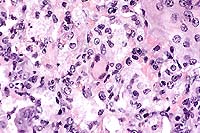

Case 3-4. Lung. Shows interstitial pneumonia with foamy alveolar macrophages and giant cells and eosinophilic, intracytoplasmic material (possibly surfactant-derived lipoproteins). 40X

AFIP Diagnoses: 1. Lung: Pneumonia, interstitial, granulomatous, diffuse, severe, with intra-alveolar eosinophilic bodies, µMT/µMT deficient mouse, rodent, etiology consistent with Pneumocystis carinii. 2. Lung, histiocytes and multinucleated giant cells: Intracytoplasmic eosinophilic spicular material.

Conference Note: Conference participants noted the eosinophilic spicular material referenced in diagnosis #2 above. The nature of the material is not clear, but most likely it consists of surfactant-derived lipoproteins. Also discussed was the presence in some sections of multifocal perivascular accumulations of small round cells with plasmacytoid features, resembling plasma cells. Since B cell development in the homozygous µMT-deficient mouse is arrested at the stage of pre-B cell maturation,3 participants wondered if the presence of these apparent plasma cells indicated incomplete penetrance of the mutation.